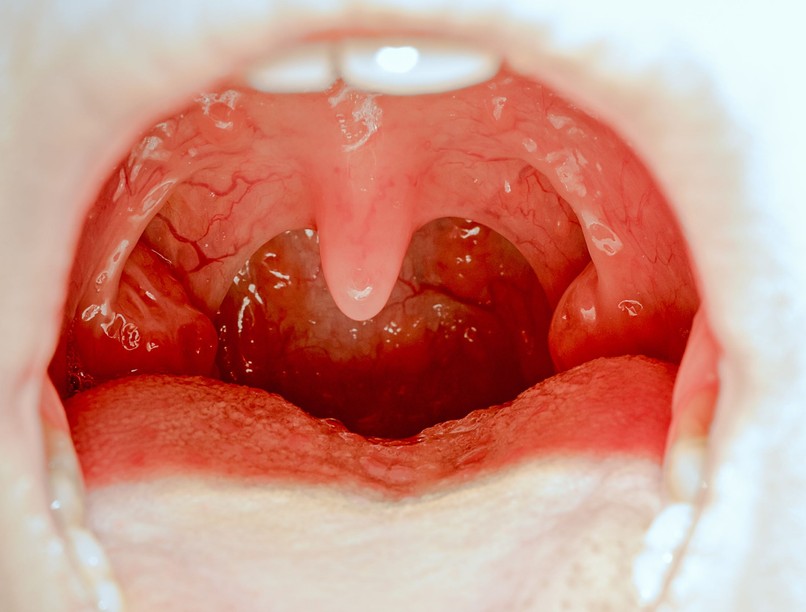

Az Epstein-Barr vírus által okozott fertőző betegség a torok hátsó részén és a mandulákon látható szinte összefolyó fehér foltok mellett lázat, torokfájást, nagy nyaki nyirokcsomókat és erős fáradtságérzetet okozhat. Ez utóbbi akár hónapokkal a többi tünet megszűnését követően is megmaradhat.

5. Mandulakő

Mandula kövek akkor keletkeznek, ha az összegyűlt anyag (kórokozók és egyéb anyagok, elhalt sejtek és nyák) megkeményedik és a mandulák járataiban marad. Ezek olykor szabad szemmel is látható fehér foltokat okoznak a mandulákon. A mandulakő legjellemzőbb tünete a rossz lehelet.

A legtöbb mandulakő nem kemény, inkább gumiszerű anyag, és a mirigyek redőiben képződik. Általában 1-2 mm átmérőjűek, de előfordulhatnak akár 1 cm-es darabok is. A mandulakövek többnyire nem okoznak semmilyen tünetet, gyakran csak torok- vagy fogászati vizsgálat, esetleg röntgen alkalmával fedezik fel őket.

A mandulakő jelenlétére utalhat:

• rossz lehelet,

• rossz szájíz,

• gyakori köhögési inger,

• fülfájás,

• torokfájás,

• nyelési nehézség,

• apró fehér foltok a mandulán.